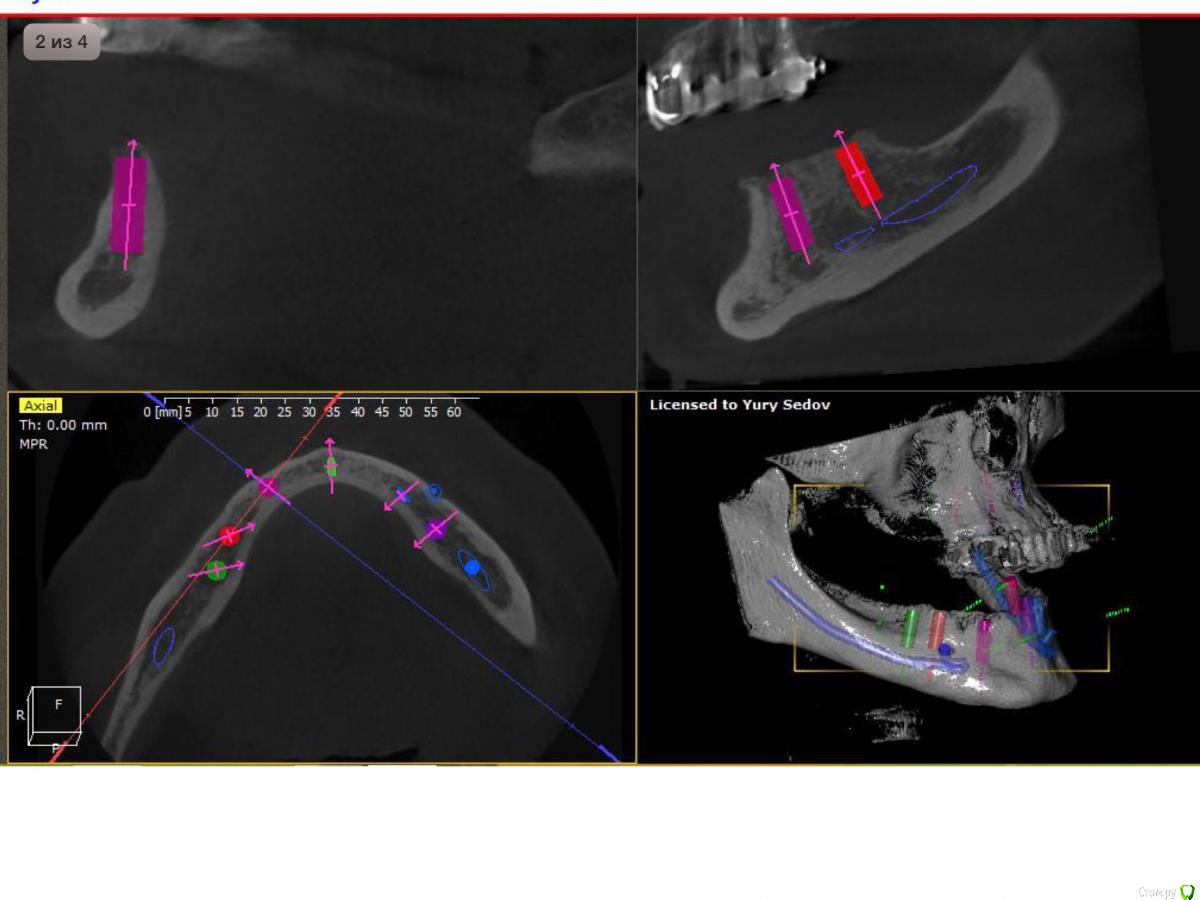

Neilrus Опубликовано 26 мая, 2015 Поделиться Опубликовано 26 мая, 2015 Здравствуйте, подскажите как быть в моей ситауции. Такого объема лечение я еще не выполнял. Беззубая н/ч. Планируем несъемное, "все на 6". Спланировал шаблон по кт на 6 имлантатов, жду его приезда из Москвы. Имплантаты mis m4. 3,8*11,5 и 10.0Планируется так же костная пластика одновременно в районе постановки имплантатов (где-то расщепление, где-то досыпка)Вот отсюда и вопрос, если мы ей пластику делаем, как сдать ей её же временный съемный протез на котором мы ей сейчас прикус зафиксировали? не держать же ее 2 месяца без протеза. У меня вариант в голове только с временными микроимплантатами с шариками Mis, диаметром 3.0 их я смогу и без шаблона поставить.А) Ни разу не делал такой конструкции, так возможно? Б) Двух микроимплантатов в позиции клыков или четверок достаточно? Через какое время можно их нагрузить? В) Ничего что они будут стоять либо между двумя пластиками, либо вообще сквозь ламину (или evolution).Г) Есть какие-нибудь более правильные варианты? Ни один из поставленных имплантатов нагружать не хочу, формики тоже при условии пластики ставить не рискну, опыт еще не тот.Д) профиль челюсти изменится, станет шире, в протезе, если его сдаем, нужно спилить базис немного и сделать перебазировку эластичной пластмассой? Спасибо всем за советы заранее)) сорри если что не так или если повторил тему, не нашел в форуме ответ. Ссылка на комментарий

Neilrus Опубликовано 29 мая, 2015 Автор Поделиться Опубликовано 29 мая, 2015 Сделайте срезы планнинга по каждому имплантату. Там будет понятно.46з45з44з 34з35з36з Может можно воссатновить на двух микроимпл только от клыка до клыка чтобы губа не западала и для сохранения высоты? Ссылка на комментарий